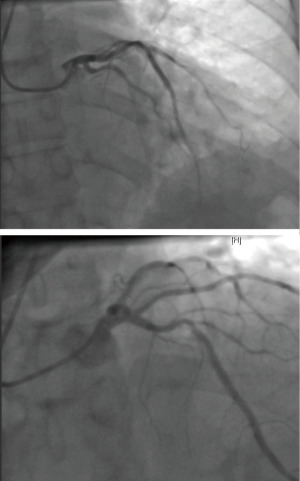

A 63-year-old woman with a medical history significant for stage IV lung adenocarcinoma with brain metastases, atrial fibrillation, peripheral artery disease, and deep vein thrombosis (DVT) on Apixaban, presented to the hospital with a 1-week history of nausea, vomiting, chest pain, and intermittent shortness of breath. She described the chest pain as pressure-like, localized to the lower chest, and denied orthopnea, paroxysmal nocturnal dyspnea (PND), or lower extremity swelling. On physical examination, she appeared mildly distressed and diaphoretic. Heart and lung auscultation were unremarkable. ECG revealed a new right bundle branch block (RBBB) without ST-segment elevation or depression. The cardiac monitor showed supraventricular tachycardia with a heart rate of 150 bpm. Laboratory investigations showed elevated troponin (938 ng/L), creatinine (1.29 mg/dL), and C-reactive protein (CRP) (219 mg/L). Chest computed tomography (CT) scan ruled out pulmonary embolism (PE). The patient was started on heparin infusion for possible acute coronary syndrome and received adenosine and intravenous metoprolol which normalized her heart rate. Transthoracic echocardiogram (TTE) revealed normal LV size and thickness but mildly decreased LV systolic function with apical ballooning consistent with Takotsubo cardiomyopathy (Figure 1, Video 1). Left heart catheterization (LHC) ruled out obstructive disease (Figure 2), leading to the cessation of ACS treatment, and the patient was discharged.

Ten days later, she returned with worsening chest pain, shortness of breath, and fatigue. ECG showed normal sinus rhythm with nonspecific T-wave abnormalities and occasional premature ventricular complexes (Figure 3). Laboratory tests revealed significantly elevated troponins (4,915 and 5,521 ng/L), and BNP (5,818 pg/mL). Repeat TTE showed severely decreased LV function, dilated and hypokinetic right ventricle (RV), and no specific regional wall motion abnormalities, reducing suspicion of cardiac ischemia. Repeat LHC was not performed. The patient was started on intravenous methylprednisolone for treatment of immune-mediated myocarditis secondary to pembrolizumab and discharged with a wearable cardioverter defibrillator. In terms of her oncological history, the patient had stage IVB lung adenocarcinoma with brain and nodal metastases. Molecular testing revealed programmed death-ligand-1 (PD-L1) expression of 0%, tumor mutational burden of 10, and mutations in STK11, TP53, and KEAP1, with no actionable EGFR or ALK alterations. Based on the KEYNOTE-189 trial (11), she was treated with carboplatin, pemetrexed, and pembrolizumab (200 mg IV per cycle) for five cycles, followed by maintenance pembrolizumab and pemetrexed. She tolerated therapy well without other treatment-related adverse events until the development of suspected immune-mediated myocarditis, which prompted discontinuation.